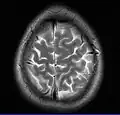

Normal axial T2-weighted MR image of the brain

- T2-weighted (T2W) images: CSF is light, but fat (and thus white matter) is darker than with T1. T2-weighted images are useful for visualizing pathology.[26]